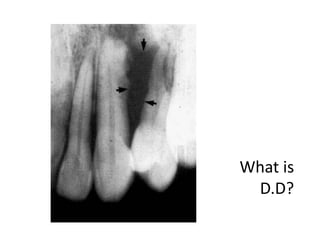

Honeycomb-like small

ameloblastoma at early stage with

evidence of root resorption.

Describe? D.D?

• What is the D.D? Solitary irregular periapical

radiolucent area related to

upper left lateral and

causing extensive

interproximal bone loss of

the adjacent tooth.

D.D:

• Chronic alveolar abscess

• Chronic osteomyelitis

• Osteoradionecrosis

• Squamous cell carcinoma

• Metastatic tumors to the jaws

• Osteosarcoma and

chondrosarcoma

• Fibrous dysplasia (early stage)

What is

D.D?